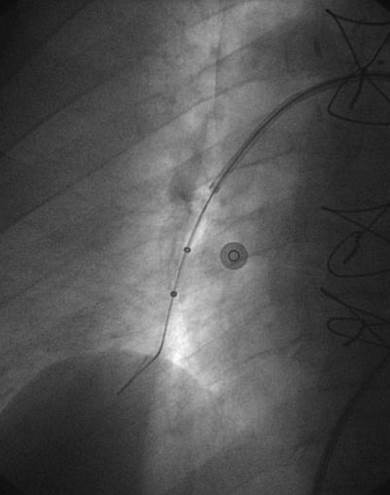

Paciente con hemorragia gastrointestinal activa que impide el uso de trombolíticos. Angiografía de la arteria pulmonar principal (más selectiva a la derecha) realizada con un catéter en espiral de 6 F en ángulo, que muestra la presencia de un trombo de gran tamaño dentro de las arterias pulmonares izquierda y derecha, y en las respectivas bifurcaciones lobares.

Se efectuó una trombectomía reolítica con el catéter PE de AngioJet® a través de una guía de angioplastia hidrófila de 0,035’’, partiendo de la arteria pulmonar izquierda y la bifurcación lobular inferior. La intervención se repitió en la arteria pulmonar derecha y en las bifurcaciones lobulares correspondientes. La intervención se detuvo debido a una bradiarritmia. Además, el tiempo de activación total se encontraba cerca del  límite recomendado (4 minutos).

A pesar del gran volumen de trombo eliminado, el angiograma final solo muestra una leve mejora de la obstrucción. Sin embargo, el objetivo del tratamiento es simplemente restaurar el flujo y no eliminar el trombo por completo, ya que incluso el modesto resultado de este angiograma estuvo acompañado de una considerable recuperación hemodinámica y de intercambio gaseoso.